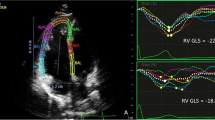

Cardiac magnetic resonance

Patients were imaged on a 3 T CMR scanner (Achieva, Philips Medical Systems, The Netherlands) with a 6-element phased-array surface-coil. The CMR protocol comprised electrocardiographically gated cine imaging with steady-state free precession (repetition time TR = 3.4 ms; echo time TE = 1.2 ms; in-plane spatial resolution = 1.5 mm) for LV and RV volumes/function, and imaging of late gadolinium enhancement (LGE) for scar assessment as previously described18. A breath-hold Look-Locker spoiled gradient-echo cine technique19 was used for T1 measurements in a single mid-ventricular slice with a temporal resolution of 80 ms for pre-contrast T1 and 55 ms post-contrast (TR/TE/flip-angle = 5/2.2 ms/10°; slice thickness = 8 mm; 192 × 128 matrix; FOV = ~ 340 × 300–340 mm; NEX = 1; SENSE = 2 parallel imaging acceleration, in-plane resolution of 1.7 × 1.7 mm)20. The Look-Locker sequence used an adiabatic inversion pulse, which by its very nature is relatively insensitive to the B1 amplitude of the radio-frequency pulses and results in excellent inversion profiles. At least 5 T1 datasets were acquired in each patient.

Assessment of biventricular volumes, function, fibrosis by CMR

The CMR images were analyzed with the MASS CMR software (Mass Research, Version 2021, Leiden University Medical Center, Leiden, the Netherlands, www.lkeb.nl) to measure biventricular mass, volumes and function21. The RV and LV walls were contoured on the Look-Locker images and divided into 4 and 6 segments, respectively. Ventricular volumes and mass were indexed by body-surface area. For the RV ECV, only the free wall from the superior to the inferior RV-to-LV insertions points was considered. T1s were determined for each myocardial segment and the LV blood pool by nonlinear least squares fitting to an analytic expression for the inversion recovery and correction for the effects of radiofrequency pulses applied using the method originally developed by Deichman and Haase22. The myocardial partition coefficient for gadolinium contrast (λGd) was determined by myocardial sector by linear least-squares fitting of pre and post-contrast R1’s in tissue against R1’s in blood. ECV was estimated as λGd multiplied by (1-Hct), where Hct represents the patient’s blood hematocrit at the time of the CMR examination23. We also estimated the LV and RV cardiomyocyte mass (CM) from the product of (1-ECV) and total LV and RV mass, respectively.

Several groups2,3,4 have demonstrated the usefulness of CMR T1 mapping in characterizing myocardial tissue remodeling of the LV in patients undergoing cancer therapy, but there are no analogous data for the RV. T1 mapping in the RV is technically more challenging. Nevertheless, studies in patients have demonstrated the value of CMR T1 mapping for detecting diffuse fibrosis in the RV. We note here that the RV ECV at baseline in our study (0.26 ± 0.07) is almost identical to the RV ECV reported for control groups in two independent studies of pulmonary hypertension (0.264 ± 0.04240, and median 0.271 with IQR = (0.251–0.279)41). There are limited data from experimental studies on longitudinal RV ECV changes following anthracycline therapy. In a rabbit model42, the ECV increased at both superior and inferior RV insertion regions from 0.28 ± 0.013 and 0.29 ± 0.02, to 0.39 ± 0.01 and 0.41 ± 0.01, respectively, 16 weeks after treatment with doxorubicin (1 mg/kg injections twice a week). The T1-based ECV estimates at the RV insertion regions correlated well with the collagen volume fraction (r = 0.824, P < 0.001)42.